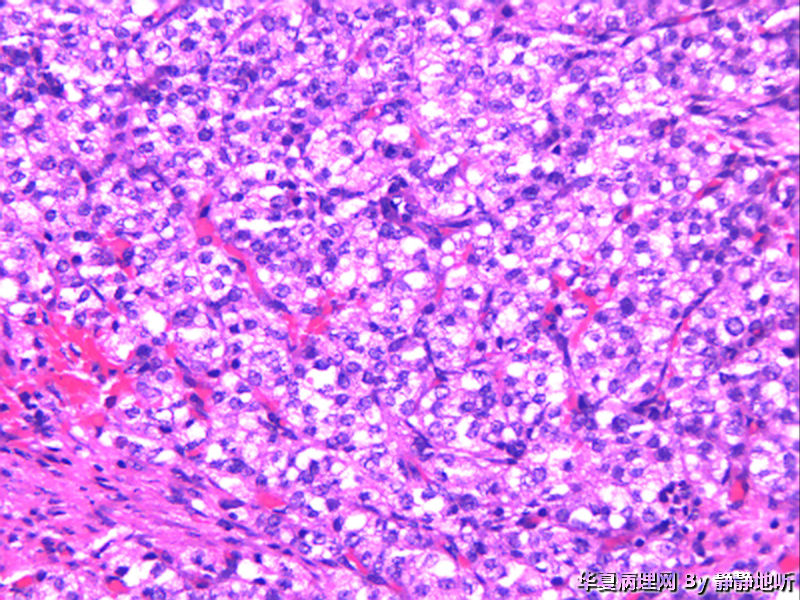

骶韧带肿物

上级医院做免疫组化:CK+ EMA+  Vimentin +  s-100 弱+  p63-   SMA血管+    CD34 血管+  HMB-45 +  Melanoma+   desmin +   ki-67约20%

会诊意见:低度恶性PEComa

女性 52岁,盆腔骶韧带肿物。肿瘤球形,直径约2.5厘米,表面光滑,切面结节状,灰粉色。镜下见大量上皮细胞巢,间质为平滑肌。免疫组化:Vimentin +   SMA梭形细胞+  EMA-   CD10-